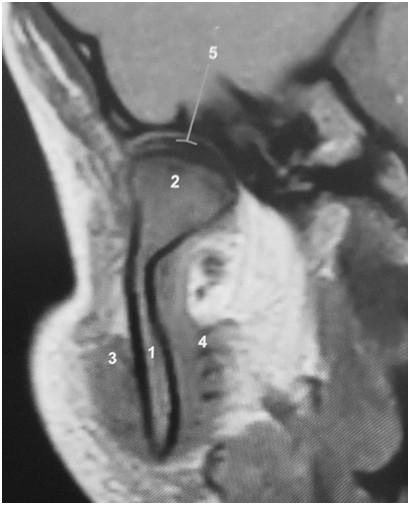

Rycina przedstawia obraz rezonansu magnetycznego, przekrój czołowy prawego stawu skroniowo-żuchwowego. Mięsień skrzydłowy przyśrodkowy jest oznaczony cyfrą: